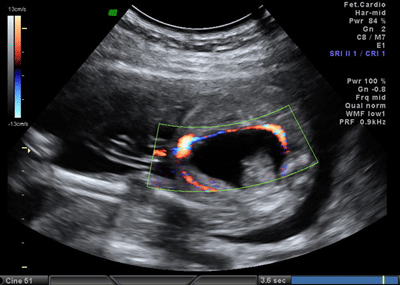

In the axial plane, besides type IV SCT (big arrow head) and hydrometrocolpos (white arrow); both kidneys (white asterix) appeared in normal loca¬tion and anatomy (Fig. 4). In the coronal plane fetal bladder (black empty arrow) was noticed (Fig. 5).

Figure 5: Fetal MRI coronal plane. |